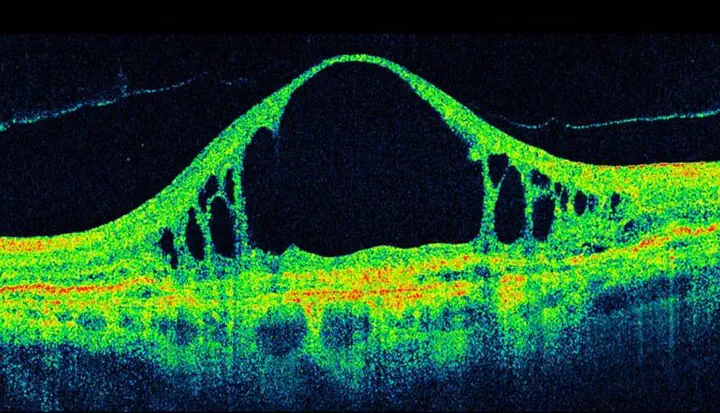

Lung Cancer Radiomics - Tumor Region Segmentation